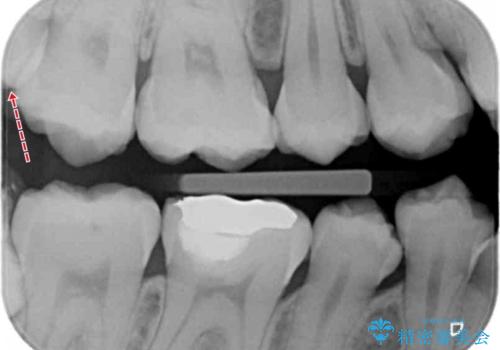

親知らずに面している歯の一部が深いところまでかなり脆くなってしまっていたため(広範囲での脱灰)、親知らずの抜歯後に精度の良いインレーを装着していきました。

親知らずが原因で手前の歯が虫歯になってしまうことがあります。

今回は親知らずの抜歯後に虫歯治療をしていきました。

親知らずが原因で手前の歯が虫歯になると、その大きさが深かった場合最悪保存が難しくなることもあります。